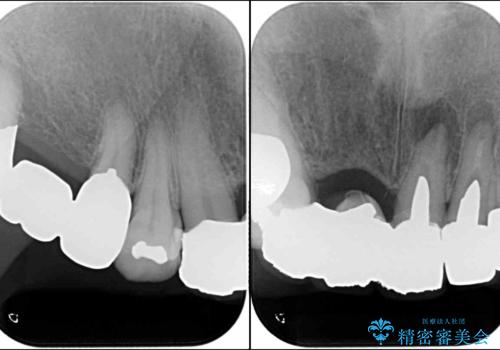

- 保険診療の前歯のブリッジが、形態も色も不自然で気になるとのことで来院された患者様です。

神経の抜かれている土台の歯は根管治療を行った上で、オールセラミックブリッジにより補綴することとしました。